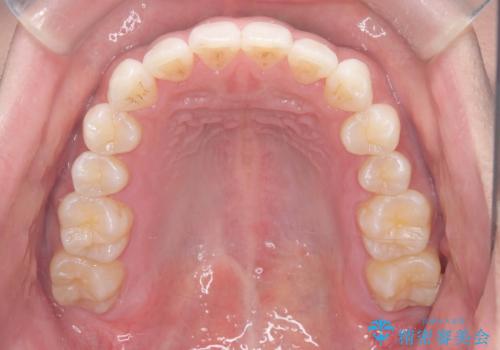

歯のデコボコを治したい|インビザラインで綺麗な歯並びに!|矯正期間は6ヵ月!

- 歯のデコボコが気になるを主訴に来院された患者様です。

インビザラインで歯は抜かずに非抜歯でデコボコを改善しました。

インビザラインで叢生の改善を行いました。

歯は抜かずに、拡大と少しのIPRで並べました。

矯正期間は半年です。

綺麗な歯並びを手に入れ大変ご満足していただきました。